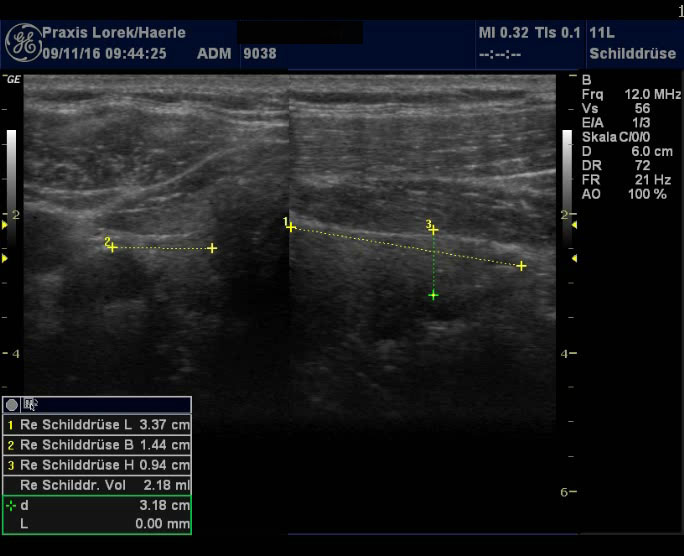

| Abb. 3 und 4: Tief liegendes

Schilddrüsenorgan bei einem 50-jährigen Mann mit deutlichen

Übergewicht, 162 cm und 103 kg. Die echoarmen subkutanen Schichten aus

Binde- und Fettgewebe sollten nicht als Schilddrüsengewebe fehlgedeutet

werden. Schilddrüse homogen, aber zu klein, TSH mit 2,25 im Normbereich,

zudem besteht ein Diabetes mellitus Typ IIb. |